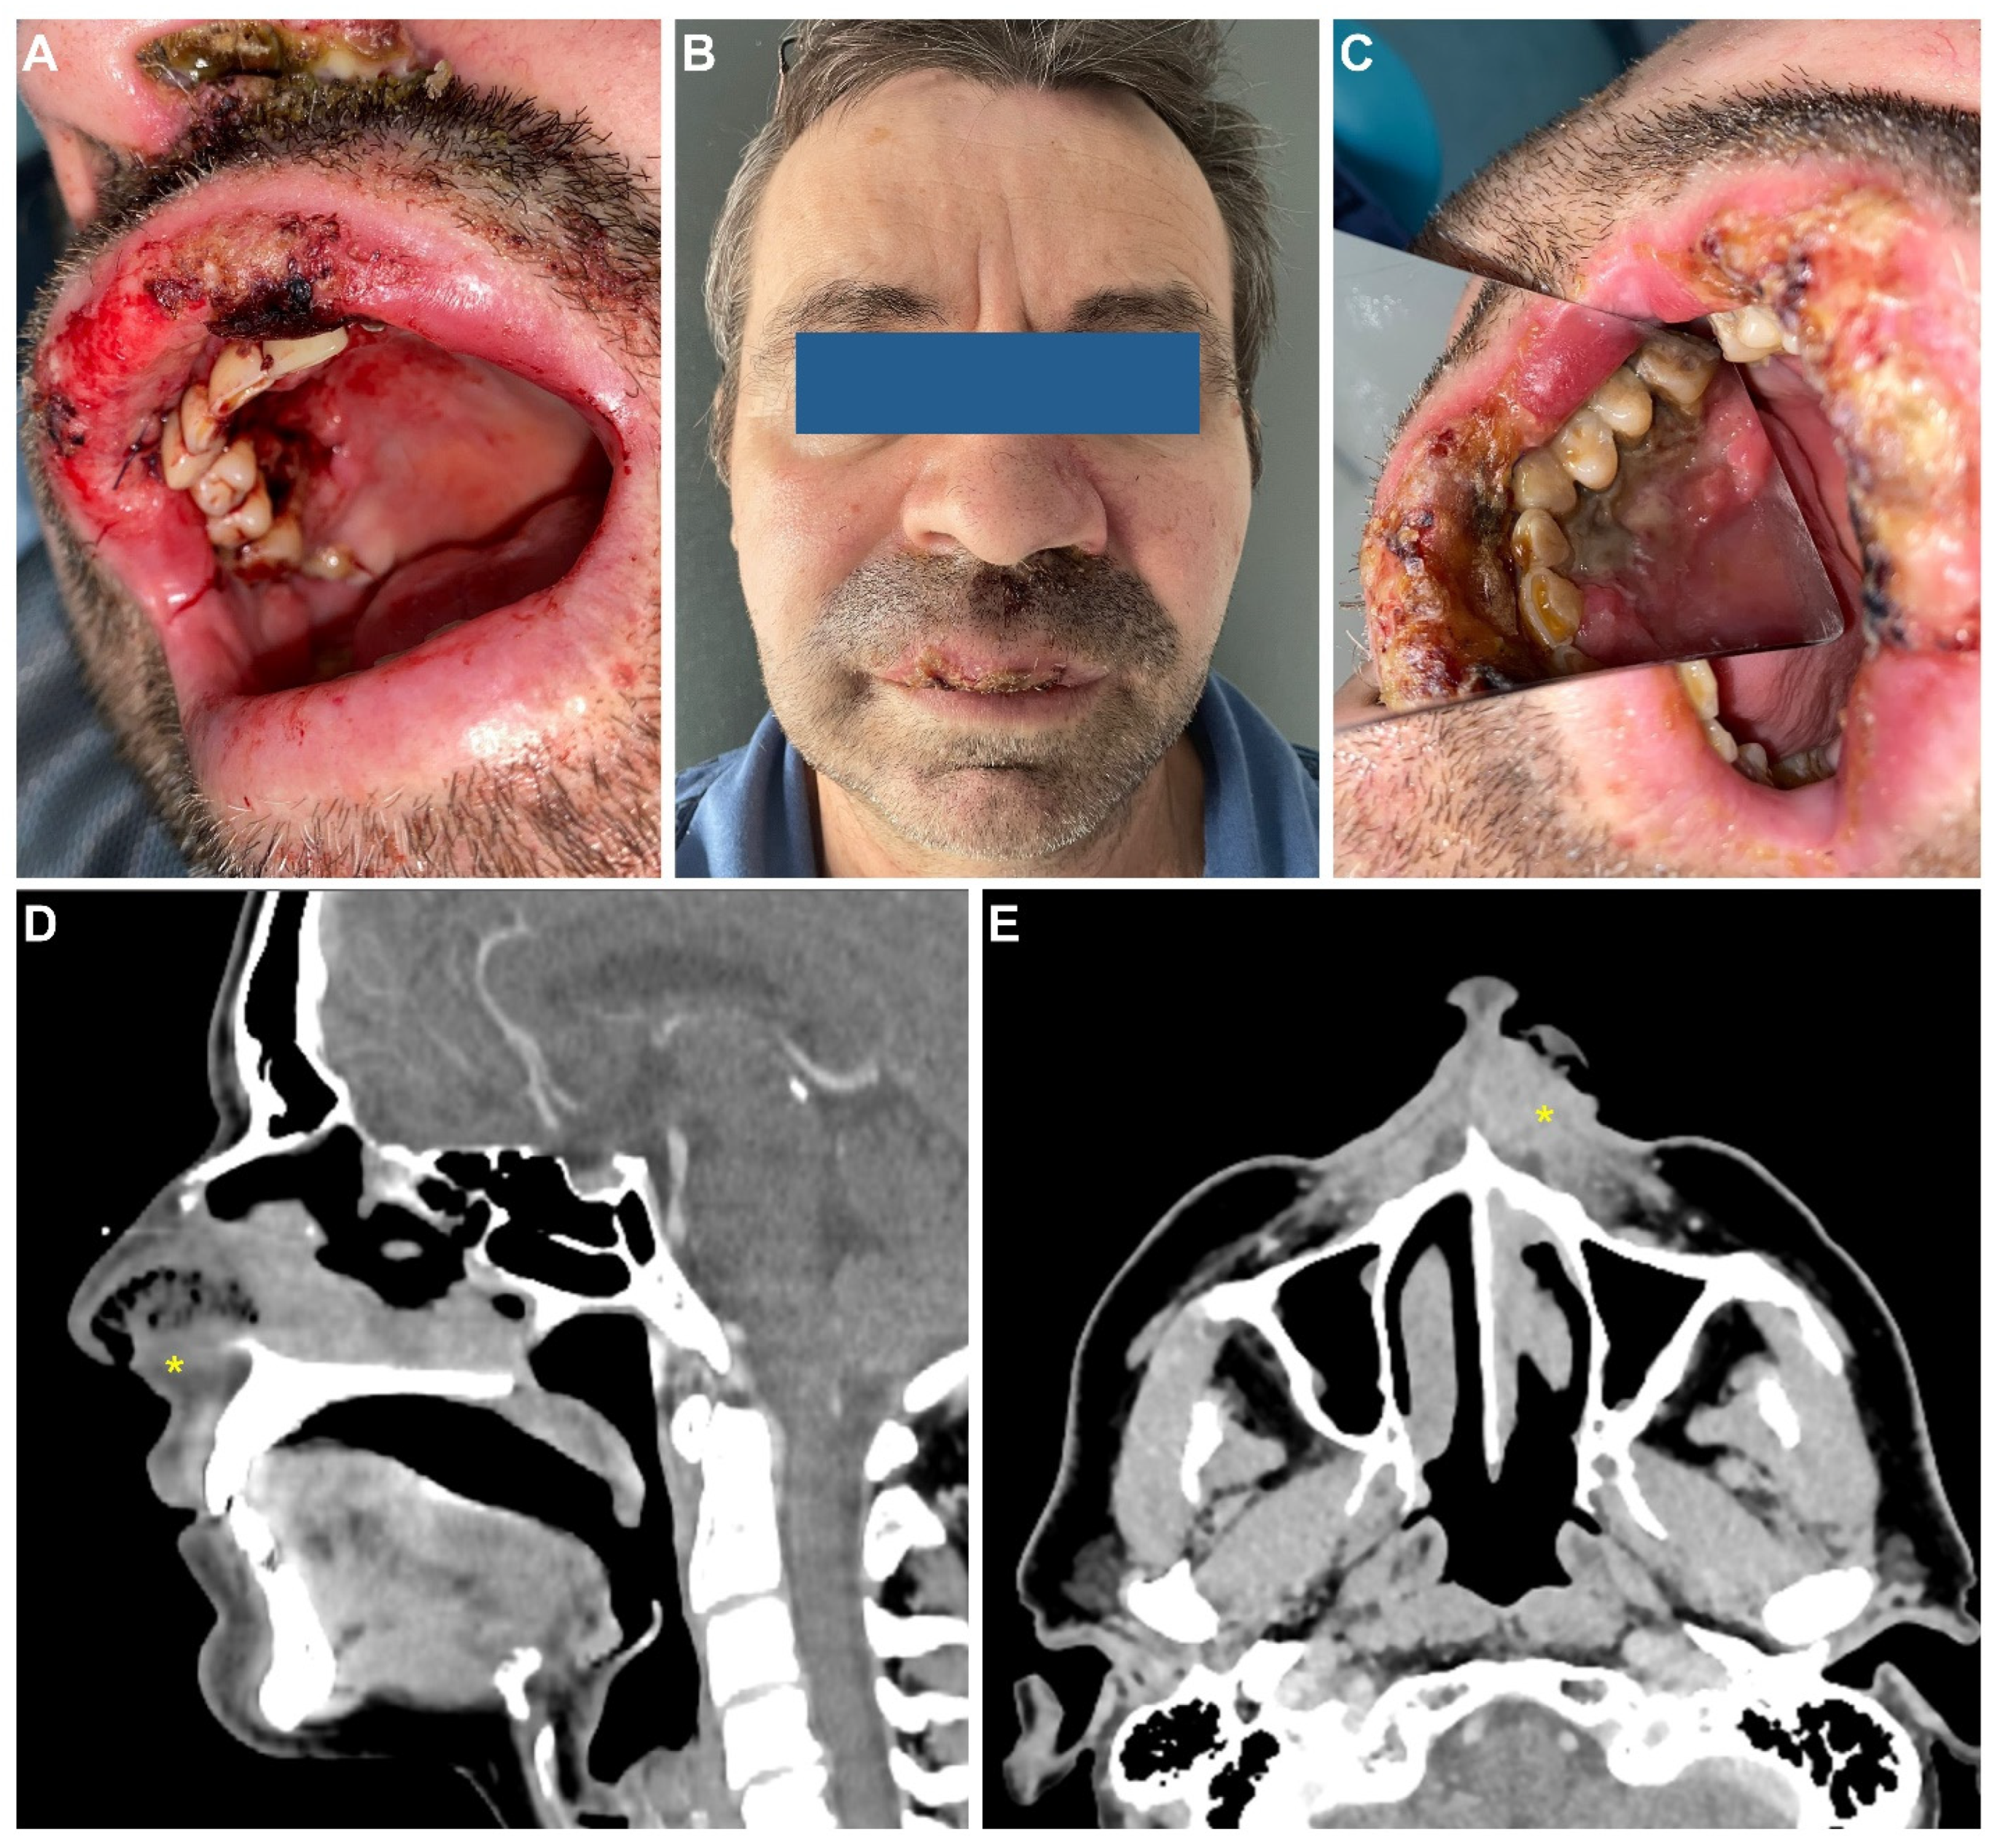

CASE 2: In December 2021, a 53-year-old male patient was referred to the Department of Oral and Maxillofacial Surgery of the “Carol Davila” Central University Emergency Military Hospital. Clinical examination revealed several erosive, overlapping, and painful lesions located on the mucosal surface of the upper lip, with diameters up to 5 mm, and normal surrounding mucosa. The lesions were progressing for about one month. In addition, the clinical assessment revealed very poor oral hygiene. The patient had recently completed a two-dose vaccination regimen against COVID-19 with the mRNA BNT162b2 vaccine: the first dose on 6 November 2021 and the second dose on 28 November 2021. Reported post-vaccination reactions were fever up to 39.5 degrees and shivering episodes during the first 24 h. On the third day after the first dose, the patient noticed the appearance of a painless ulcer on the mucosal surface of the upper lip. He initiated self-treatment with topical vitamin A. The lesion extended and new lesions developed, in spite of the therapy. Meanwhile, the second dose of the vaccine was administered and, because the oral lesions were progressing, the patient sought specialized medical assistance. The medical history revealed that the patient was under treatment for hypertension for several years (metoprolol tartrate 50 mg TID) and for anxiety (Venlafaxine 25 mg BID). He was not diagnosed with any other chronic condition and denied a personal or family history of malignancy. The patient was a construction worker and reported long-term exposure to industrial dust. He also had a 25-year history of heavy smoking (20 cigarettes/day), with complete cessation about 8 years prior. The patient denied alcohol or drug abuse. He did not complain of other symptoms, such as weight loss, fatigue, or loss of appetite, at the first visit to our department. The clinical suspicion was of infection (with herpes simplex virus) or a bullous disease with oral manifestations. The patient was referred to dermatology for further investigations and treatment. One week later, the patient was brought to the emergency room with active oral bleeding. Clinical examination revealed extensive oral ulcers involving the upper lip vermilion and mucosa, right side gingiva, and palatal mucosa, with bleeding areas and necrotic areas, intense pain, as well as swelling of the upper lip. Furthermore, new areas of necrosis covered with organic debris were identified in the left nostril (Figure 3A–C). Blood tests revealed severe anemia (hemoglobin 7.0 g/dL) with iron deficit (46 µg/dL), elevated inflammatory markers (fibrinogen- 549 mg/dL), ESR (23 mm/1 h) and increased platelet numbers (478 k/µL).

Figure 3.

Clinical and imaging aspects at presentation. Intraoral aspect at the presentation to the emergency room, after superior labial artery ligature (A); clinical appearance after 2 days (B,C); contrast-enhanced CT scan of the neck in the sagittal (D) and axial (E) planes. Heterogeneous infiltrative mass (*) of the upper lip, left inferior nasal vestibule, and left inferior turbinate.

The patient was admitted to our department for emergency treatment. Under local anesthesia, the source of active bleeding was identified as the superior labial artery and was ligatured; the patient received a transfusion with one unit of blood. Diagnostic investigations were initiated. The patient tested negative for COVID-19, hepatitis B and C, and HIV. A bacterial swab from the ulcer revealed infection with Pseudomonas aeruginosa, sensitive to all types of antibiotics. Immunology tests revealed abnormally elevated values for C4 serum complement and serum Ig E (43.9 mg/dL and 536.6 UI/mL, respectively). No other abnormal findings were detected after the general assessment. The head and neck contrast CT scan revealed reactive bilateral cervical lymph nodes and irregular thickening of the upper lip, the lateral wall of the left nasal vestibule, and the inferior turbinate (Figure 3D,E). Multiple site incisional biopsies were collected from the ulcerated areas: gingiva, palatal, and nasal mucosa. The pathology results described an intense polymorphous lymphoid infiltrate in the epithelium, represented by small- or medium-sized cells, with incised or angulated nuclei and moderate cytoplasm (Figure 4A). Immunohistochemistry (IHC) revealed tumor proliferation with T cells, with the following characteristics: diffuse positive staining for CD3 and CD7, diffuse positive staining for granzyme B, positive staining for CD30, and frequent cells with low-intensity CD56 staining (Figure 4B–E). IHC staining was negative for CD4, CD8, and CD20. The findings were compatible with the diagnosis of extranodal malignant non-Hodgkin lymphoma with T/NK cells.